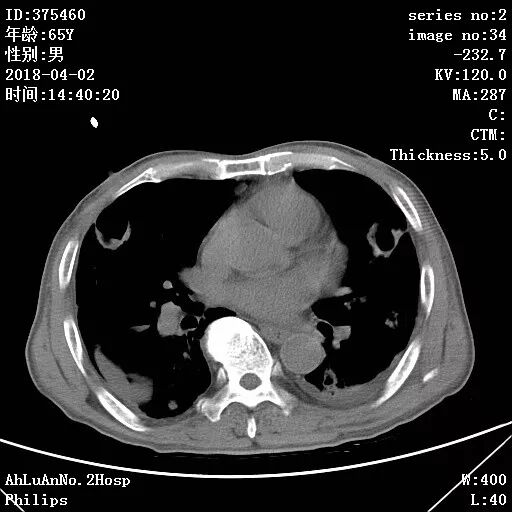

患者男,65岁,因“咳嗽、咳痰1月余,发热1周”入院。

两肺可见多发斑片状及气囊样阴影,部分气囊样影内可见气液平面,两侧胸膜腔可见少量液性密度影聚集。

结果:金黄色葡萄球菌肺炎